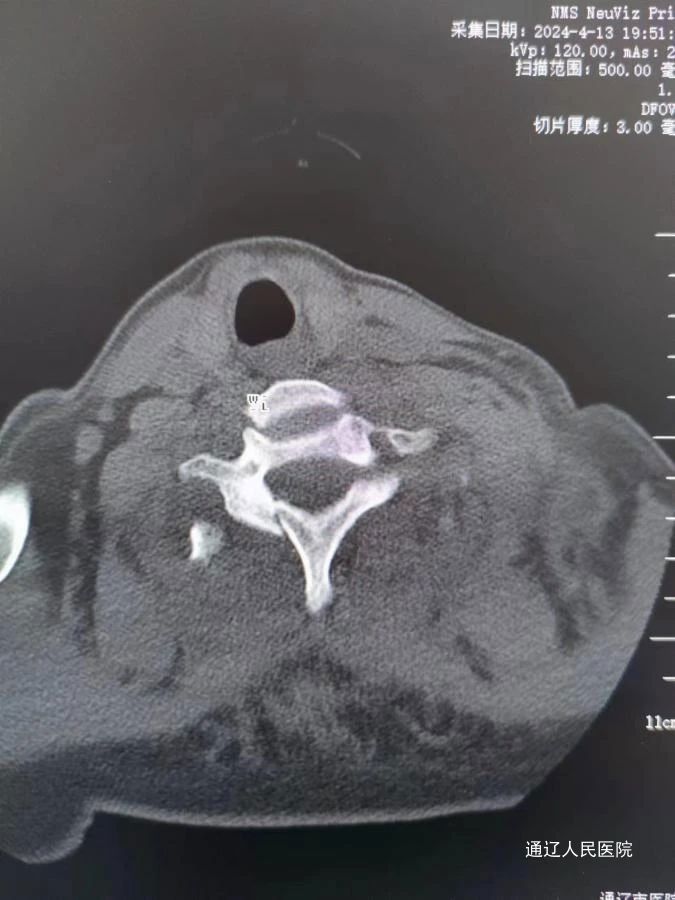

近日,我院脊柱外科在科室负责人房芳的带领下成功为一名颈7椎体骨折脱位合并截瘫的患者,施行了后入路颈椎骨折脱位切开复位减压植骨、颈椎侧块螺钉内固定、胸椎椎弓根螺钉内固定术,这项手术在骨科领域被认为是“三高”手术,即高难度、高风险、高要求,填补了我市技术空白。患者女性,68岁,因外伤致颈7椎体骨折脱位合并截瘫,由下级医院转院送至我院治疗。入院后,医院领导高度重视,迅速进行资源调配,保障及时抢救。我院医护团队立即展开积极对症处理措施,并迅速完善相关检查。考虑到患者年龄较大且病情严重,医务部组织了重症监护和麻醉团队等多学科开展联合会诊MDT。经过深入讨论和分析,专家们为患者量身定制了详尽的手术治疗方案,旨在最大限度地降低手术风险,确保患者安全。

术中减压充分、颈椎骨折脱位完全复位,内固定位置及牢固程度令人满意。在我院脊柱外科、手术室、麻醉科、ICU、输血科协力合作下手术顺利完成。术后患者生命体征平稳,双下肢感觉部分恢复。肢体可以活动。恢复康复训练后远期可生活自理。

颈胸交界处固定手术对于脊柱外科一直属于一个难点,由于在较小的颈椎和较大的胸段交界处有不同的过渡应力,靠近神经血管结构,以及复杂的解剖结构,在固定这些区域时必须极其小心和精确。作为通辽市首例颈椎胸椎联合固定手术,这项手术的成功实施,不仅体现了我院脊柱外科医生的精湛技艺,也为脊柱疾病患者带来了新的治疗希望,标志着我院脊柱外科在颈椎、高位胸椎疾病治疗方面,上了一个新的台阶。随着医学技术的不断进步,我院将不断引进和学习国际先进的医疗技术和理念,提升诊疗水平。同时,加强与国内知名医疗机构的合作,共同推动脊柱外科领域的发展,为患者健康保驾护航。